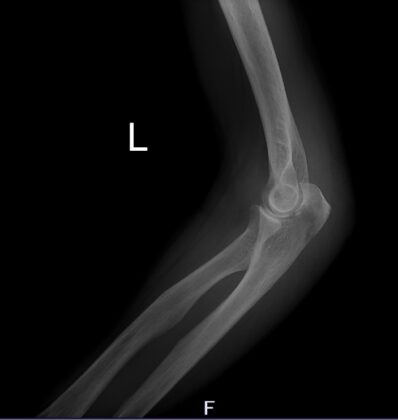

下記の患者さんは、肘頭骨折と言って肘関節での骨折です。

治癒過程で多くの事が起こりましたが、一つ一つを適切に対処することで

無事に障害なく治すことができました。